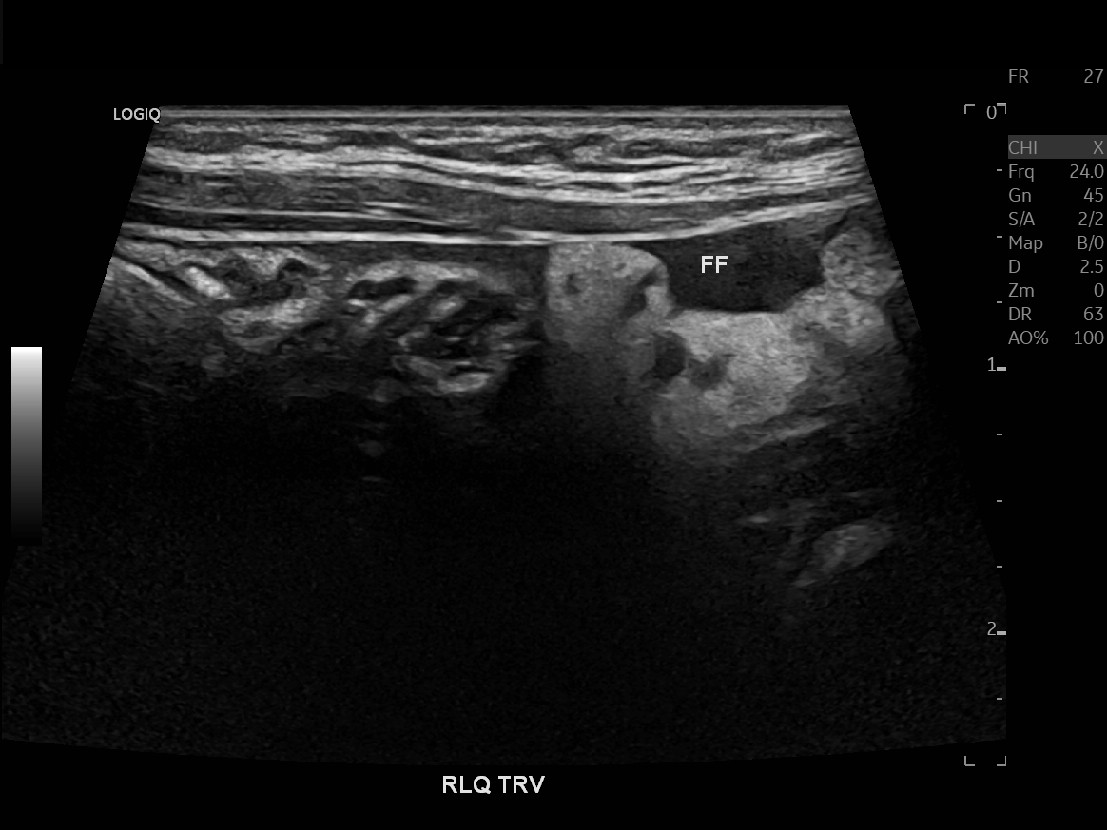

Appendicitis 15

Appendicitis 16

Hyperemia, echogenic fat and appendicolith